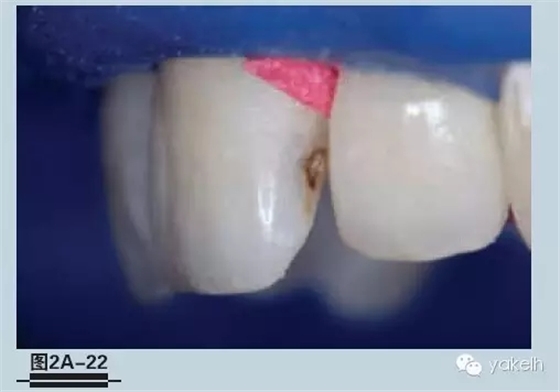

圖2A-22-用橡皮障隔離術(shù)區(qū)后,把一個(gè)木楔子放置在頸部牙齦